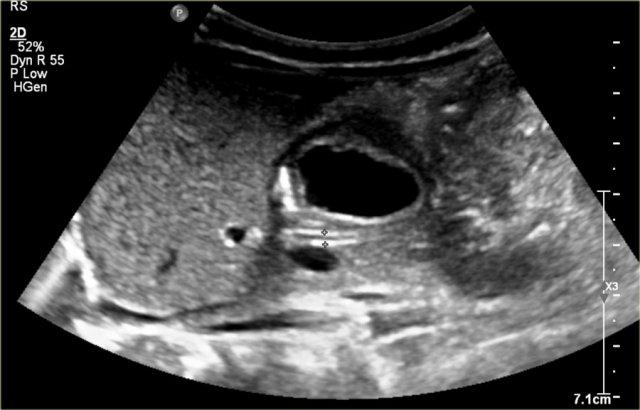

Đây là hình ảnh một nang được phát hiện trước sinh, được xác nhận sau khi sinh ở một bé gái sơ sinh.

Quan sát thấy một nang có mức dịch-dịch (fluid-fluid level).

Trong phẫu thuật, phát hiện xoắn buồng trứng trái.